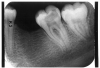

Пульпит на рентгене

Как на рентгене выглядит пульпит

Как выглядит пульпит на снимке